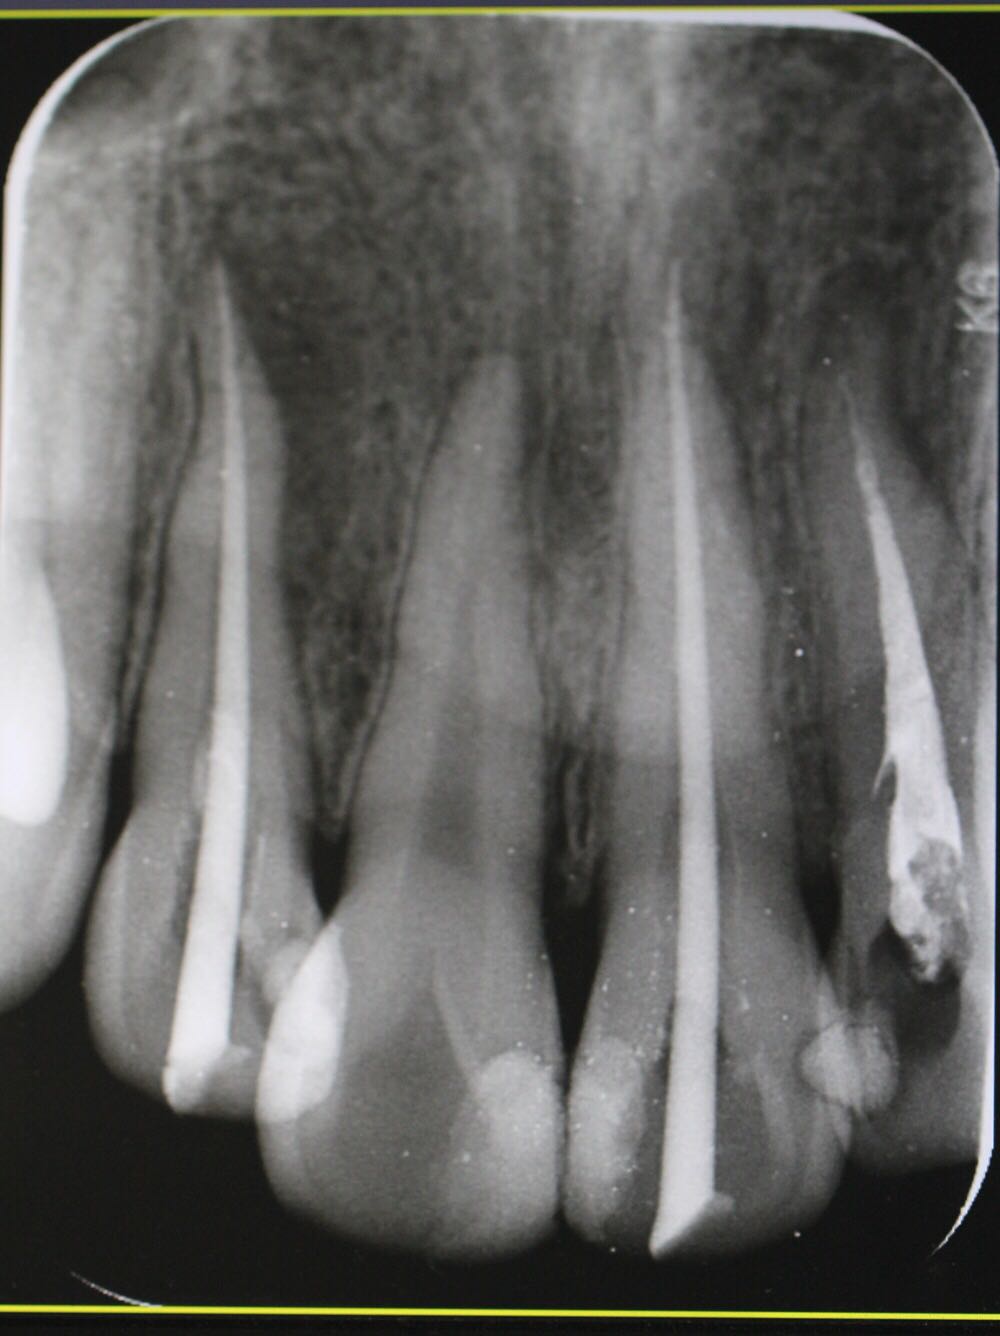

检查:12牙未见明显龋坏,探(-),冷(-),叩(++),无明显松动,牙髓电活力测试无反应,唇侧牙槽粘膜处未见窦道。 X线片:12牙根尖周暗影?

诊断:12牙牙髓坏死? 治疗方案: 1、12牙根管治疗+充填治疗+冠修复 2、12牙择期治疗 3、12牙显微根尖外科手术 4、12牙拔除 5、12牙观察 治疗计划:与患者交流沟通并详细介绍每种治疗方案、费用、时间、预后等,由于患牙根尖病变范围较大,预后欠佳。患者知情、同意并选择方案2,签署知情同意书。 12牙涡轮机开髓,探查根管口,10#,15#K锉疏通根管,根长测量仪测量根管长度,12牙22.5mm,髓腔和根管内放置根管润滑剂,S3扩锉至2506,拍片试尖,X线片示主尖合适。次氯酸啊冲洗根管,P5荡洗,纸尖干燥根管,置氢氧化钙,Caviton暂封。

处置:12牙去暂封,去棉球,根管及髓腔消毒并再次测量并确定根管长度,干燥后,显微镜下使用根尖孔生物材料加大锥度牙胶尖及热牙胶行根尖屏障封闭成形及根管充填,再拍X线片检查根充效果,X线片示根充良好,窝洞消毒,暂封。 医嘱:不适随诊,勿用患牙进食

侧切牙是畸形舌侧沟的好发牙位 釉质发生卷曲 一定程度后 可以形成牙中牙 该部位容易形成细菌通道造成根周的感染 治疗效果欠佳 在完善根管治疗后 应长期随访 必要时行外科手术 如果仍不能有效控制感染 则考虑拔牙